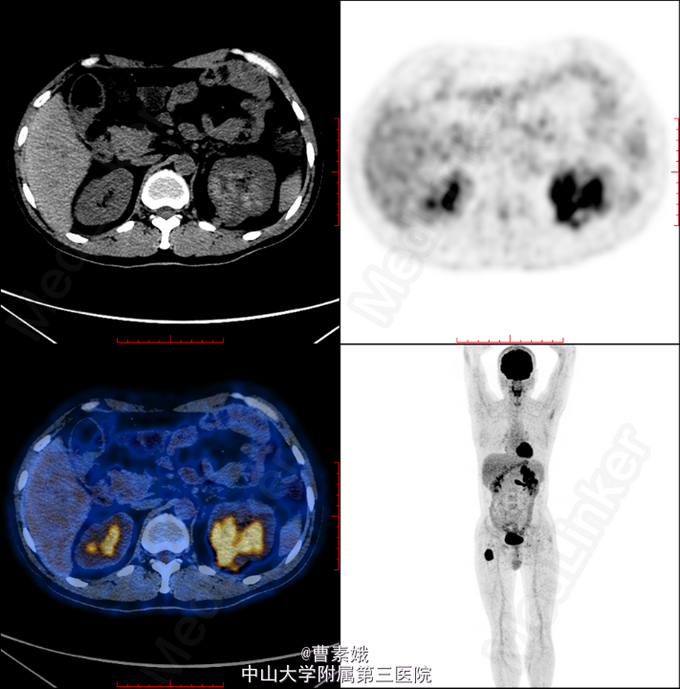

初步诊断:右股骨近端骨肿瘤(?)。 考虑右股骨肿物性质未明,遂于我院行全身PET/CT及腹部CT增强扫面,检查结果提示:1、左肾肿块并左肾静脉充盈缺损,代谢活跃,考虑左肾癌(透明细胞癌可能)并左肾静脉癌栓形成;双侧肾上腺座椅;腹膜后淋巴结转移;左侧股骨 经济股骨上段骨转移。随后患者行“左股骨肿物+左肾肿物穿刺活检术”,冰冻病理结果提示:左肾透明细胞癌,左股骨肿物考虑肾透明细胞癌转移。考虑患者肾透明细胞癌多发转移,无手术指征,转入肿瘤内科予索坦靶向治疗。